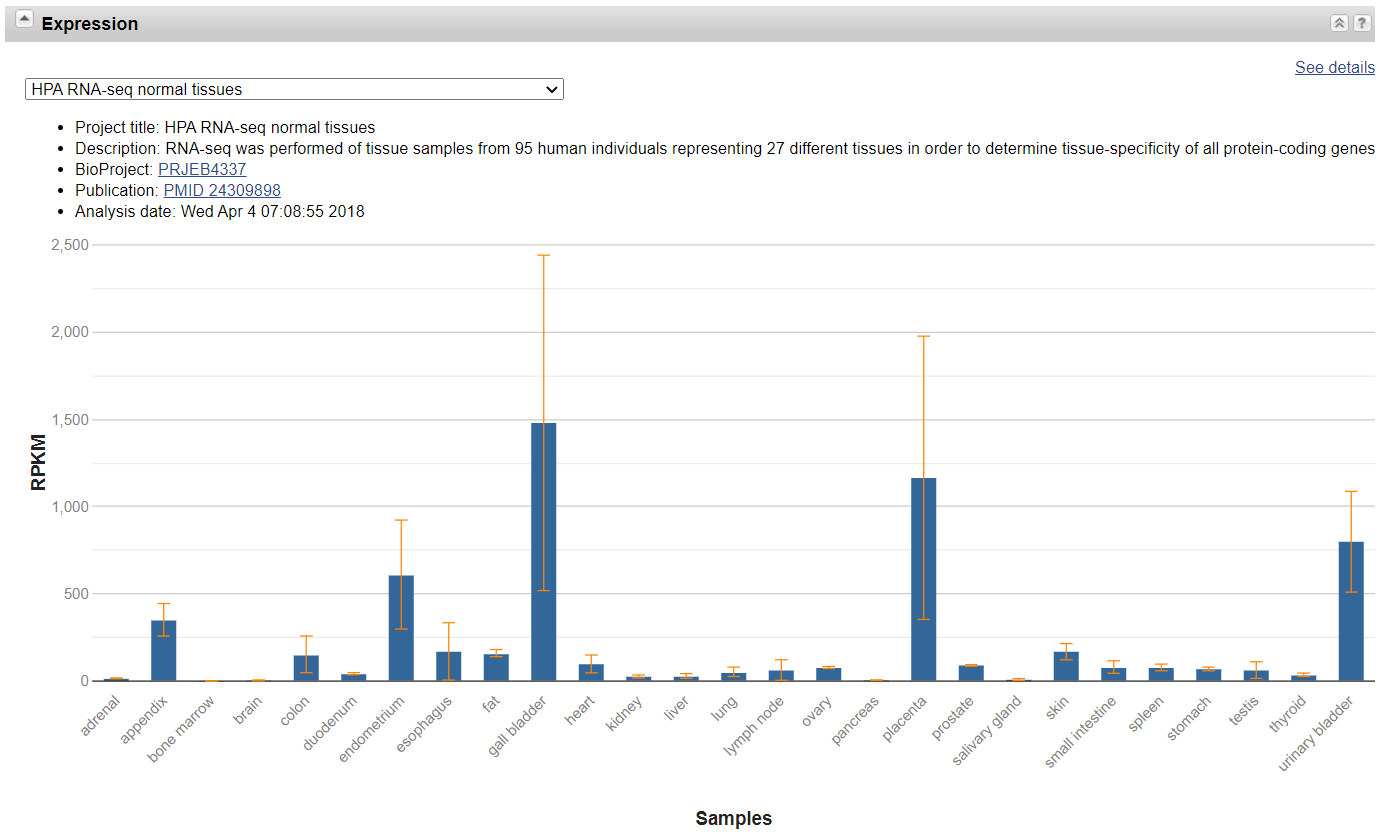

- COL3A1 基因编码的蛋白质被称为III型胶原蛋白,是同三聚体,或由三个相同的肽链(单体)组成的蛋白质,每个肽链称为III型胶原蛋白的 α − 1 α-1 α−1 链,是原纤维胶原蛋白之一,其蛋白质具有长的,不可弯曲的三螺旋结构域。

- COL3A1基因位于 2 2 2 号染色体的长臂 ( q ) (q) (q),位于 2 q 32.2 2q32.2 2q32.2 处,位置 188 , 974 , 372 188,974,372 188,974,372 和 189 , 012 , 745 189,012,745 189,012,745 之间。该基因有 51 51 51 个外显子,约 40 k b p 40 kbp 40kbp 长。COL3A1基因的尾巴方向与另一种原纤维胶原蛋白的基因,即COL5A2一致。

- COL3A1基因的突变会导致血管型Ehlers-Danlos综合征(vEDS;也称为IV型EDS; OMIM 130050)。它是EDS的最严重形式,因为患者通常由于大动脉或其他中空器官的破裂而突然死亡。